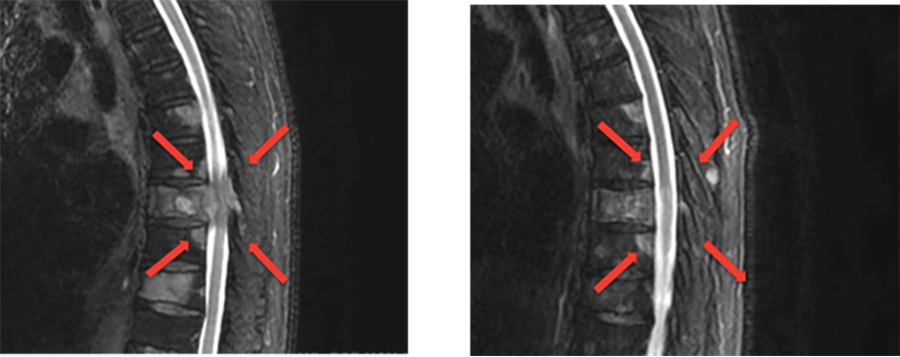

転移性脊椎腫瘍による脊髄圧迫

脊椎・脊髄腫瘍が脊髄を圧迫し、疼痛や麻痺、しびれ、膀胱直腸障害を起こす病態です。

完全な麻痺になってしまうと、治療をしても回復が困難になります。足がしびれる、動かしにくいといった症状がある場合には、すぐに手術や緊急照射を行う必要があります。